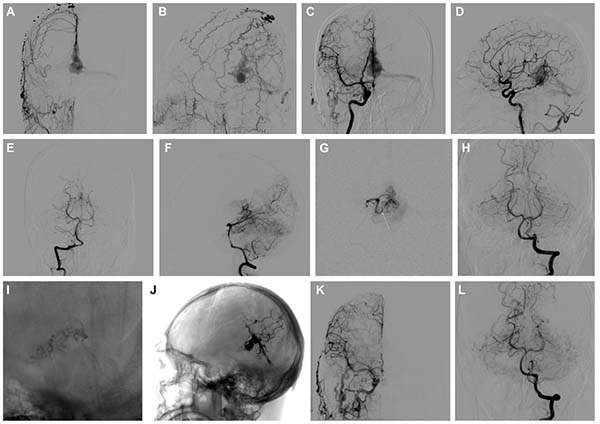

图5. A-C:该病例为右侧横窦-乙状窦区的Borden I型DAVF,可能继发于静脉窦支架植入后。患者此前曾在其他医院接受过血管内治疗。病灶区瘘口较为弥散,供血动脉来源于颈外动脉的多支硬膜分支及来自后循环的若干软膜分支。D-F:大脑后动脉和小脑上动脉的超选造影显示多条曲折的“纯”软膜及硬膜供血动脉。在栓塞过程中,将微导管尽可能置于瘘口附近,并使用Glubran进行栓塞。G-J:然而,术后MRI显示右侧小脑及枕叶出现新发梗死灶(G和H为T2加权成像;I和J为弥散加权成像)。

图6. A-C:该病例为一例位于Galen区的高级别DAVF,其供血动脉来自颈外动脉的多支硬膜分支,以及来自大脑后动脉的硬膜和“纯”软膜供血分支。D:右侧大脑后动脉的超选造影显示一条线状的硬膜供血支。E和F:此外,双侧大脑后动脉还可见曲折分支状的“纯”软膜供血支。G-I:在通过左侧PAS进行栓塞过程中,疑似发生动脉破裂。J:术后Dyna CT检查显示蛛网膜下腔出血。